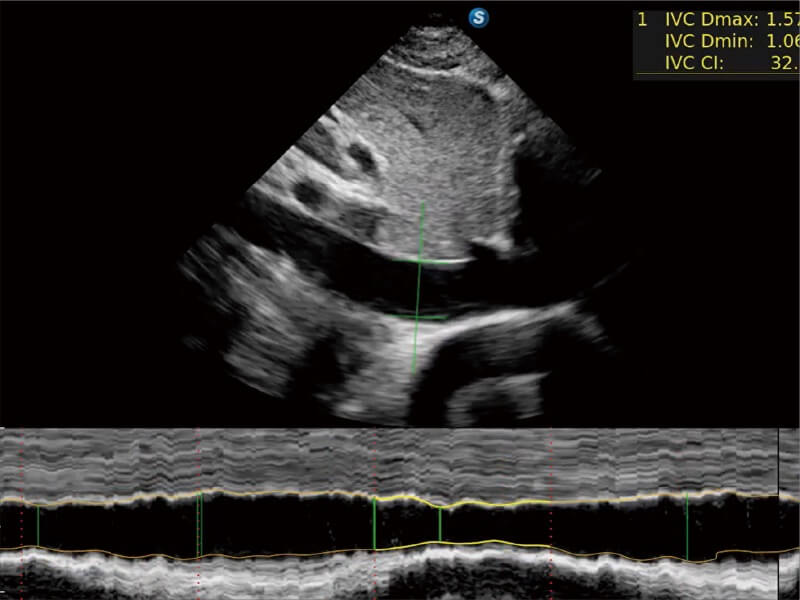

作为开立医疗全新打造的高端床旁笔记本超声,E11不仅具备卓越的图像质量,同时搭载全面高效的自动测量工具,助力医生实现更快速、更精准的床旁诊断。

E11搭载了丰富的自动化测量工具,以及专为POC科室定制的高级功能;同时配备了为急诊医师量身打造的 SonoFast急重症超声流程,以帮助临床医生最大限度的提升工作效率